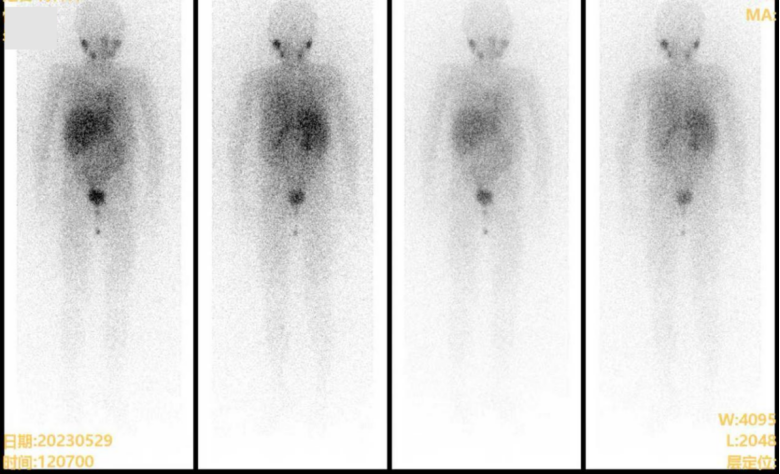

2023.05.29 外院MIBG:腹膜后神经母细胞瘤术后,腹膜后、双侧盆壁缘及骶前多发软组织密度结节影,I-MIBG显像阴性;脊柱多发椎体及骨盆诸骨骨质密度欠均匀,MIBG未见摄取,Curie评分0分(0,0,0,0,0,0,0,0,0,0)。